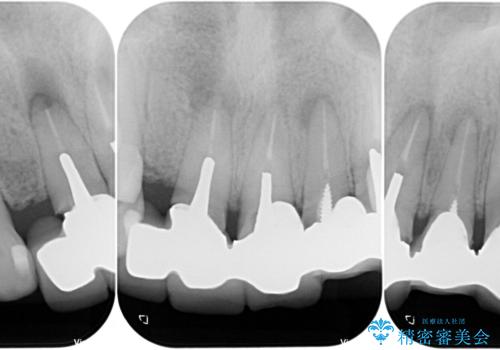

受け口を無理やりブリッジで改善したことで、支台歯の1本は歯根が破折しており抜歯が必要な状態でした。

根管治療がされている歯の一部には根尖部の違和感があり、根管治療が必要と判断されました。

抜歯および根管治療を実施した後にオールセラミッククラウンにて補綴することとしました。